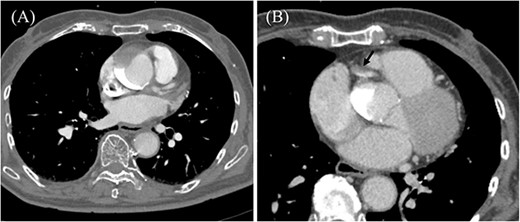

An 85-year-old woman with a history of hypertension and cerebral infarction presented to the emergency department of another hospital with the complaint of temporary loss of consciousness (LOC). Dehydration was suspected to be the cause of LOC; however, CAG was performed to confirm the reason for the mild elevation in creatine kinase and D-dimer levels. While the left coronary system was intact (Fig. 1A), the coronary dissection spread retrogradely from the right sinus of Valsalva to the ascending aorta after injecting contrast into the right coronary artery (RCA). The RCA was completely occluded at the proximal part, and no collateral flow into the RCA was observed (Fig. 1B). Electrocardiography revealed previously undetected ST elevation in leads II, III, and aVF and reciprocal ST depression in leads I, aVL, and V4–6 (Fig. 2). Contrast-enhanced CT confirmed aortic dissection which was localized in the ascending aorta (Fig. 3A). Additionally, RCA occlusion at the proximal portion was suspected (Fig. 3B). The patient was transferred to our institute for further management of the aortocoronary dissection. On arrival, the patient was alert and oriented with close to normal vital signs. Echocardiography showed a normal left ventricular ejection fraction with preserved RV function; however, severe hypokinesis of the inferior wall was noted. Moreover, as the hemodynamic status of the patient gradually deteriorated in the emergency department, we decided to perform an emergency surgery.

Preoperative contrast-enhanced CT. (A) Ascending aortic dissection is detected. Contrast-material is pooled in the false lumen. (B) Dissection at the proximal part of RCA is suspected (black arrow).